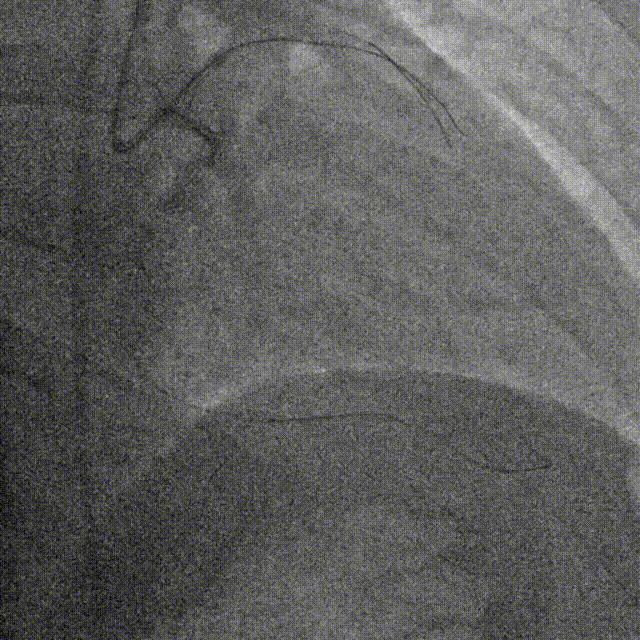

D1释放DCB,LAD植入支架后D1血流影响,工作导丝找回后使用球囊扩张并kissing。

造影发现LAD远端病变仍较重,释放DCB。

复查造影并行ivus检查 支架贴壁良好 无累及夹层。

RCA中段扩张后出现夹层,植入DES。